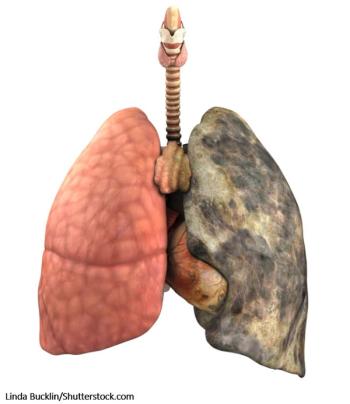

Beth is age 52, smokes 2 packs of cigarettes a day, gets breathless in cold weather, and has had "bronchitis" twice this year. What's your diagnosis?